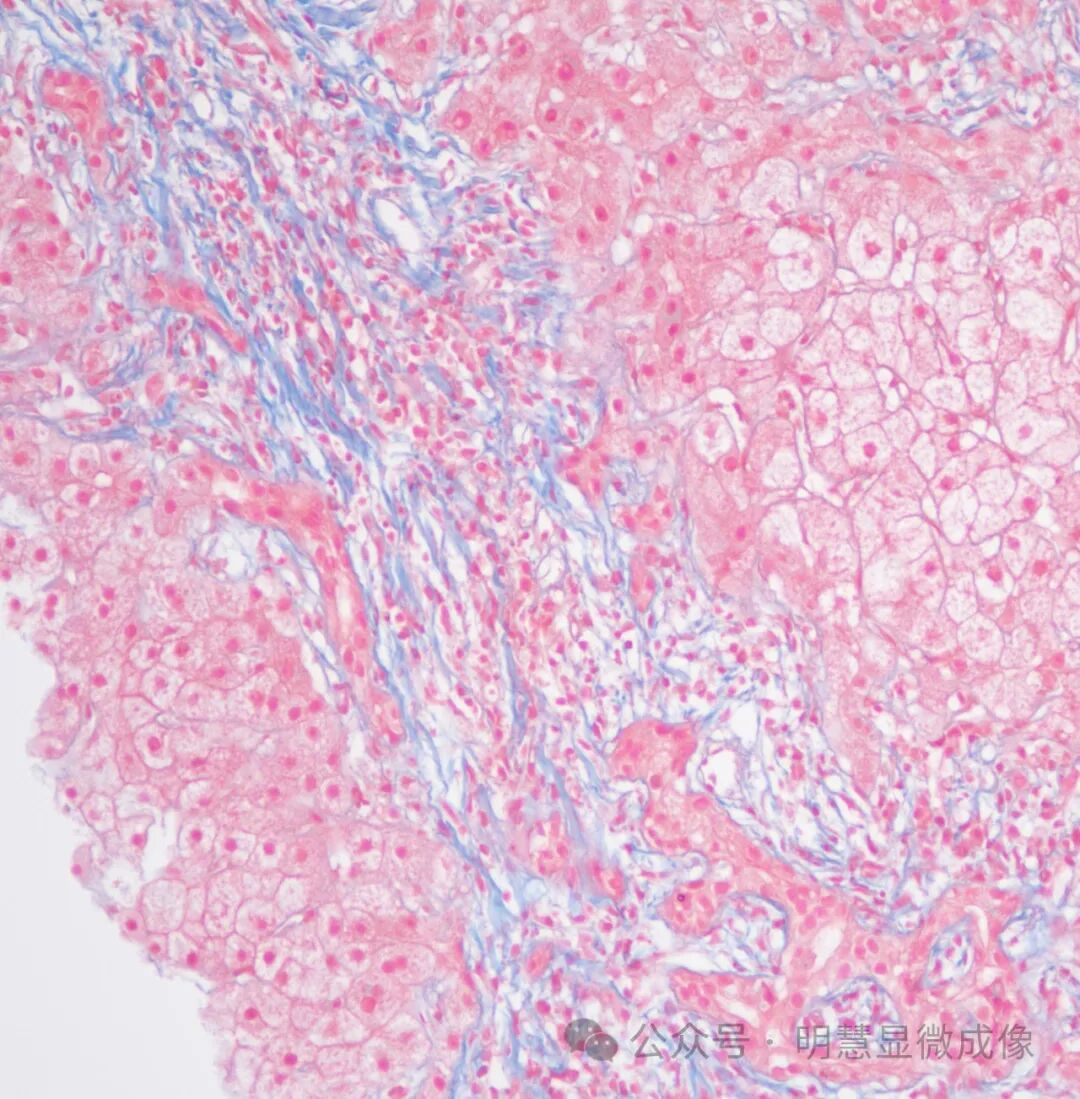

惭贬顿2000实拍效果图